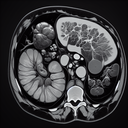

МРТ органів черевної порожнини

Магнітно-резонансна томографія (МРТ) органів черевної порожнини – це високоточний метод діагностики, який дозволяє отримати детальне зображення внутрішніх органів та структур. Процедура допомагає виявити різноманітні захворювання, такі як пухлини, запалення, та інші патології. Переваги МРТ органів черевної порожнини: 1...